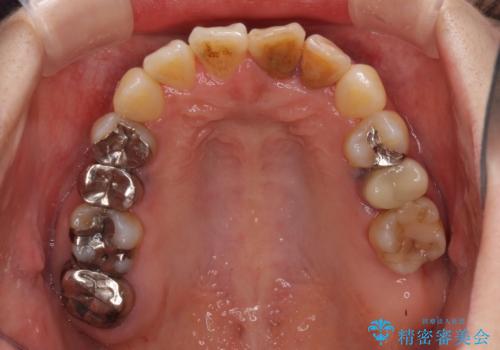

骨格的に下顎が前方位にありますが、歯列矯正で前歯の被蓋関係を改善することができると判断されたため、インビザラインにより矯正治療を行うこととしました。

また、上顎前歯と下顎大臼歯に神経を取り除いた歯があったため、矯正治療後に、セラミッククラウンにて補綴することとしました。